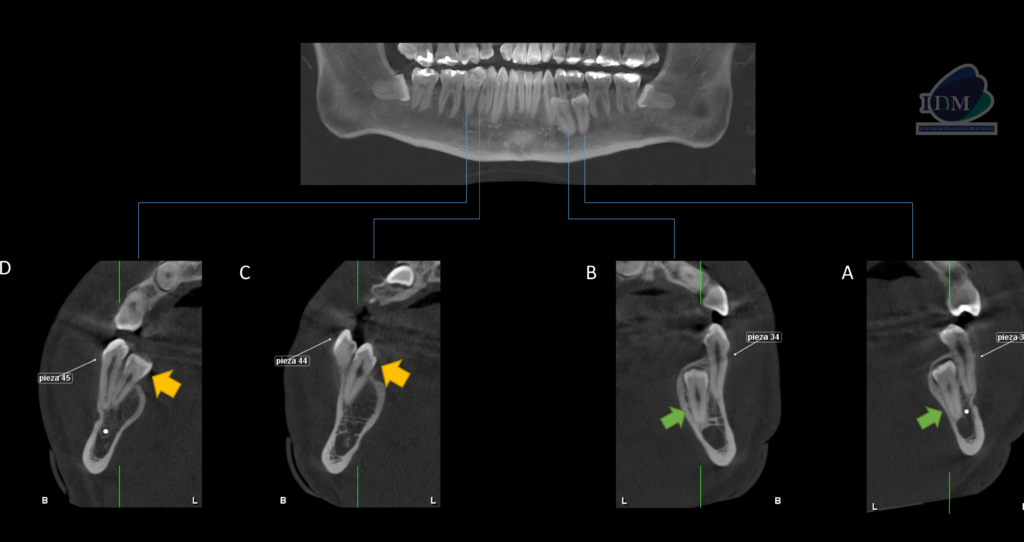

A la evaluación de la tomografía computarizada se puede observar la posición exacta de los cuatro supernumerarios mandibulares suplementarios, así como la relación con las piezas dentarias adyacentes y estructuras anatómicas importantes. Las flechas de color verde indican la posición del supernumerario A hacia lingual con la porción coronaria en contacto con la pieza 35 y el tercio apical en contacto con la cortical del conducto dentario inferior, así también el supernumerario B en estrecha relación con la superficie lingual de la pieza 34 (vista en cortes axiales, transaxiales y tangenciales).La flecha de color amarillo indican la localización por lingual de los supernumerios C Y D en estrecha relación con la superficie lingual de las piezas 44 y 45 respectivamente. En ambos cuadrantes se observa la giroversión y el desplazamiento hacia vestibular de las premolares.

CORTES TANGENCIALES

CORTES TRANSAXIALES